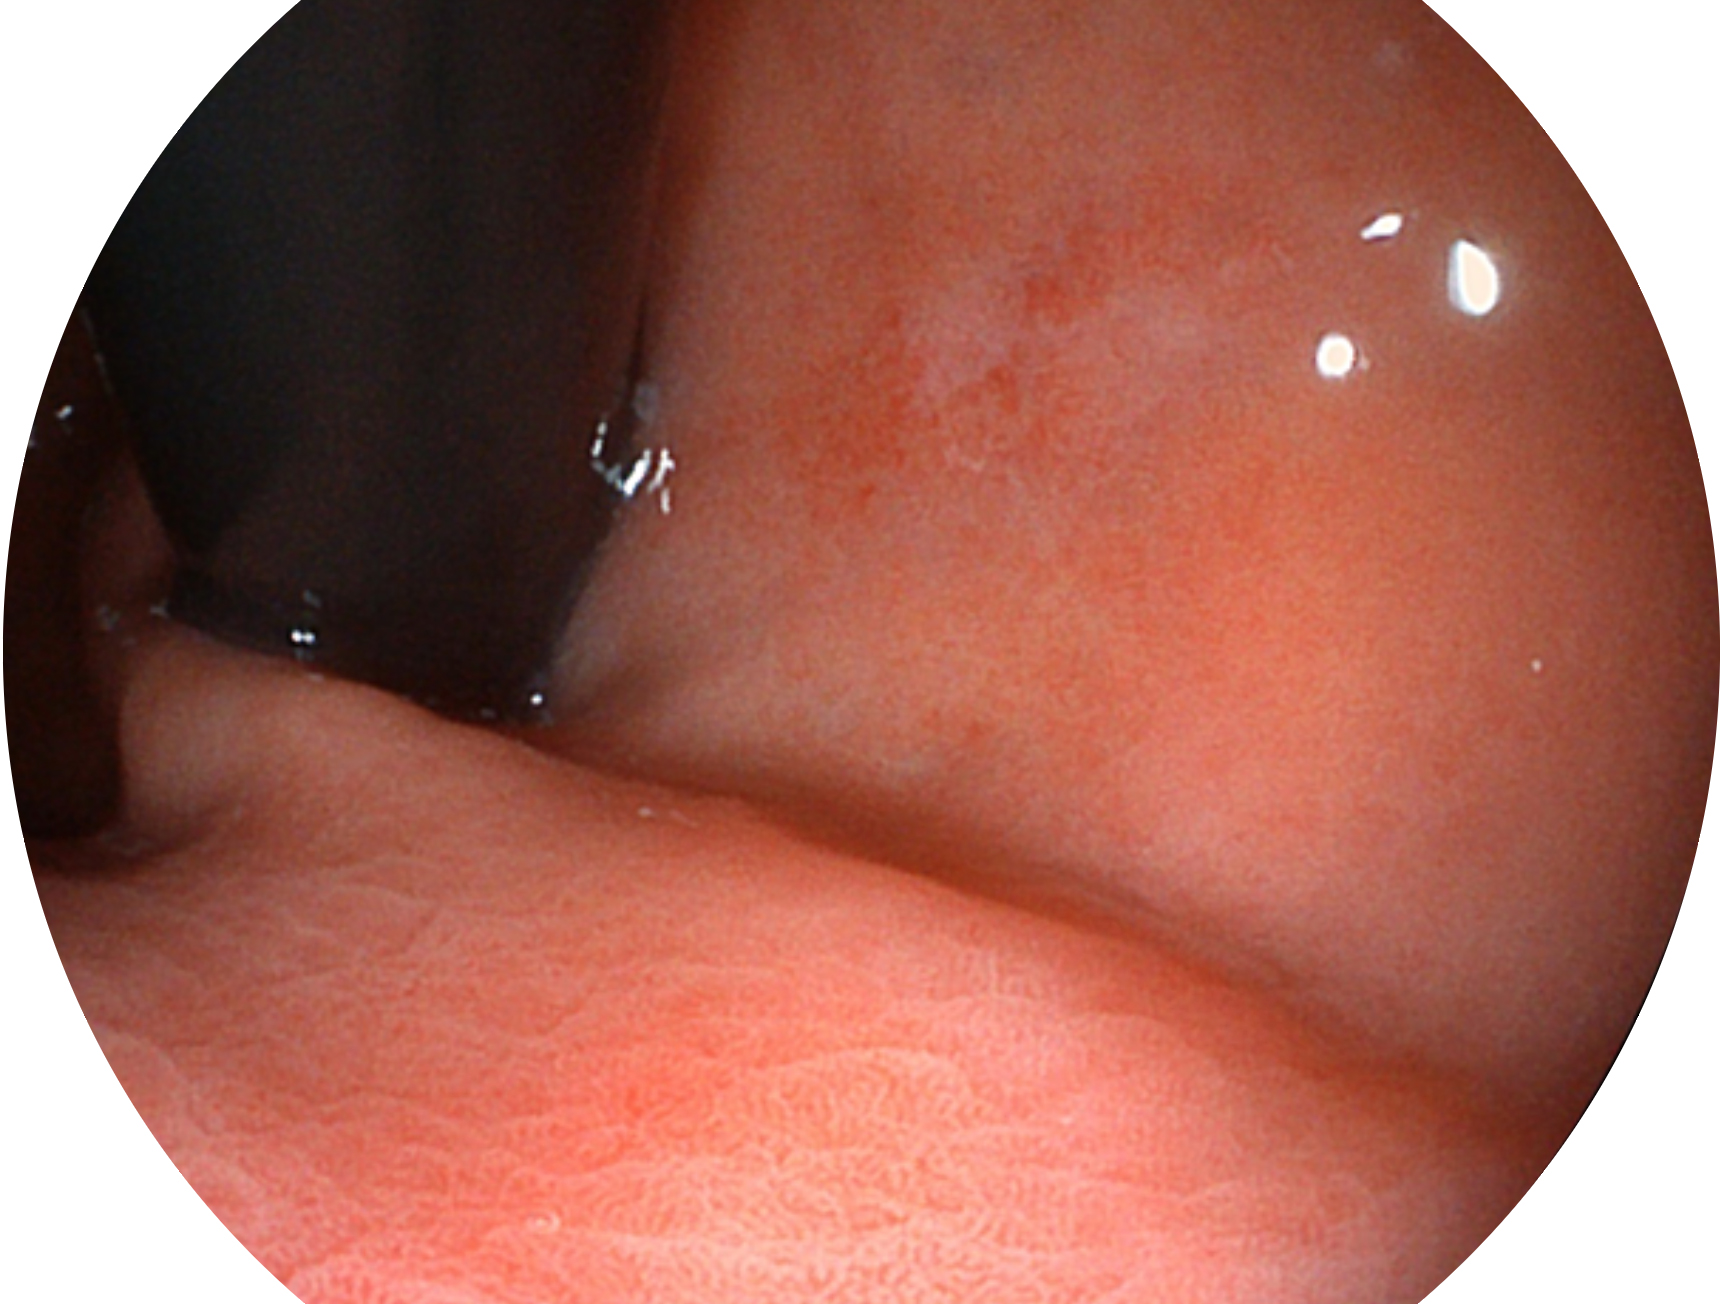

DB中国旗舰官方网站新开发的内镜染色技术,主要是基于多波长LED 光源的开发,VLS-55Q 四波长LED 光源是由四个不同颜色的LED光按照相应照明模式所规定的特定发光比例进行合束后形成,合束后形成的照明光的光谱由红光、绿光、蓝光及蓝紫光这四个不同的波段范围构成。具有更高光谱自由度,通过光谱比例的控制,实现了聚谱成像技术,英文全称为“Spectral Focused Imaging, SFI”,缩写为“SFI”和光电复合染色成像技术,英文全称为“Versatile Intelligent Staining Technology, VIST”,缩写为“VIST”。